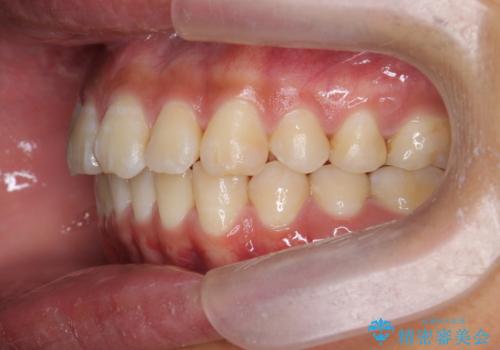

遠心移動を伴うマウスピース非抜歯矯正治療

マイクロインプラントを使用したことで、しっかりと遠心移動が為され、良好な咬合関係が達成されました。